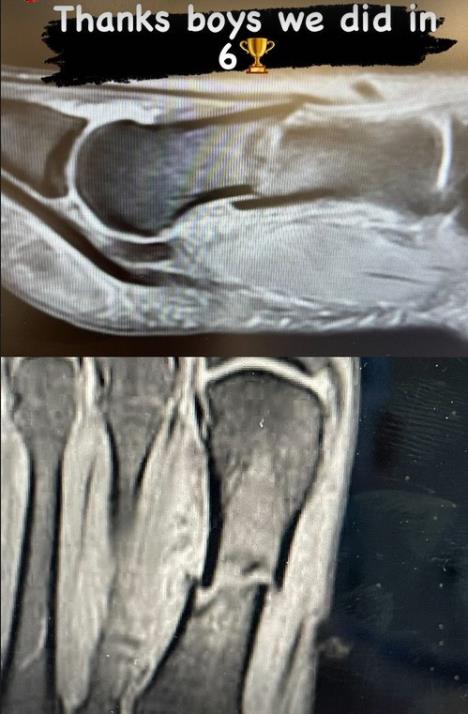

Jedan od junaka trijumfa Kolorada je ruski hokejaš Valeri Nikuškin. Rus, ne samo da je u odlučujućem meču bio strelac, nego je na ledenu ploču izašao sa teškim prelomom noge. Ruski hokejaš je objavio i kako izgleda rendgenski snimak njegovog stopala, gde se jasno vidi prelom.

Foto: Instagram